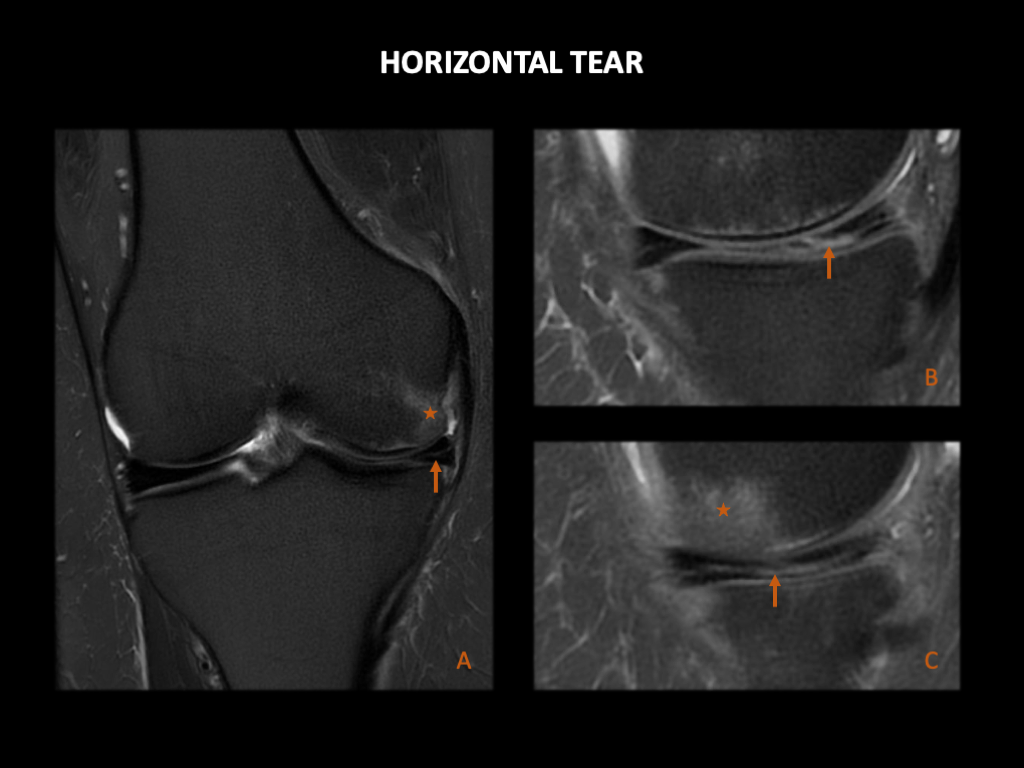

水平撕裂:它们是最常见的半月板撕裂,倾向于发生在内侧半月板的体部或后角。在40岁以上的人群中,无相关膝部损伤的退行性基础上更为常见。

图 5: 一名43岁男性,有急性膝痛病史。右膝3T MRI:(A)冠状位T2加权脂肪抑制序列和(B)及(C)矢状位PD脂肪抑制序列显示内侧半月板体部和后角高T2信号,与水平撕裂相符(箭头所示)。半月板体部向内侧副韧带位移(半月板挤压)。股骨内侧髁可见骨髓水肿(星号)。